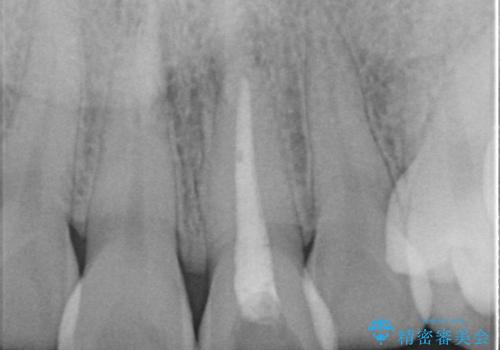

- 他院で前歯の変色をダイレクトボンディングにて修復治療しておりましたが、審美障害を主訴に来院されました。

根管治療後、オールセラミックにて治療を行っております。

根管治療の注意事項(リスク・副作用など)

- 根管治療により類似の全ての症例の問題が解決するわけではなく、症例はあくまでも一例です

- 根管治療により痛みや腫れがひかない事や、術後に痛みや腫れが生じる事、治療によるファイル破折やパーフォレーションなどの偶発症、術後の歯根破折を生じる可能性もあります